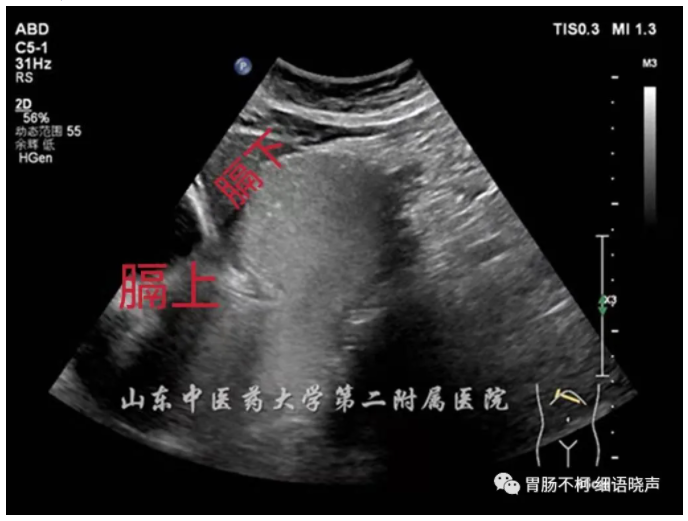

滑动型:EGJ上移,膈肌裂孔内径正常或增宽(正常解剖内经1.8-2.5cm),膈上疝囊及膈下胃呈“葫芦状”,“烧瓶状”,吸气、增加腹压、右侧卧位或二次充盈时疝囊及膈肌裂孔增大,造影剂在裂孔上下往返,膈上疝囊壁厚度及回声与胃壁一致相延续。

混合型:EGJ位于膈上,其旁可见部分胃移至膈上,两囊呈“双头征”。

下图是不同表现的滑动型食管裂孔疝:宽窄不一的食管裂孔管径、大小不一的疝囊、或正常或变钝的HIS角,部分病例可见疝囊壁与胃壁回声及厚度一致的延续:

病例三,混合型食管裂孔疝,膈上两囊呈“双头征”: